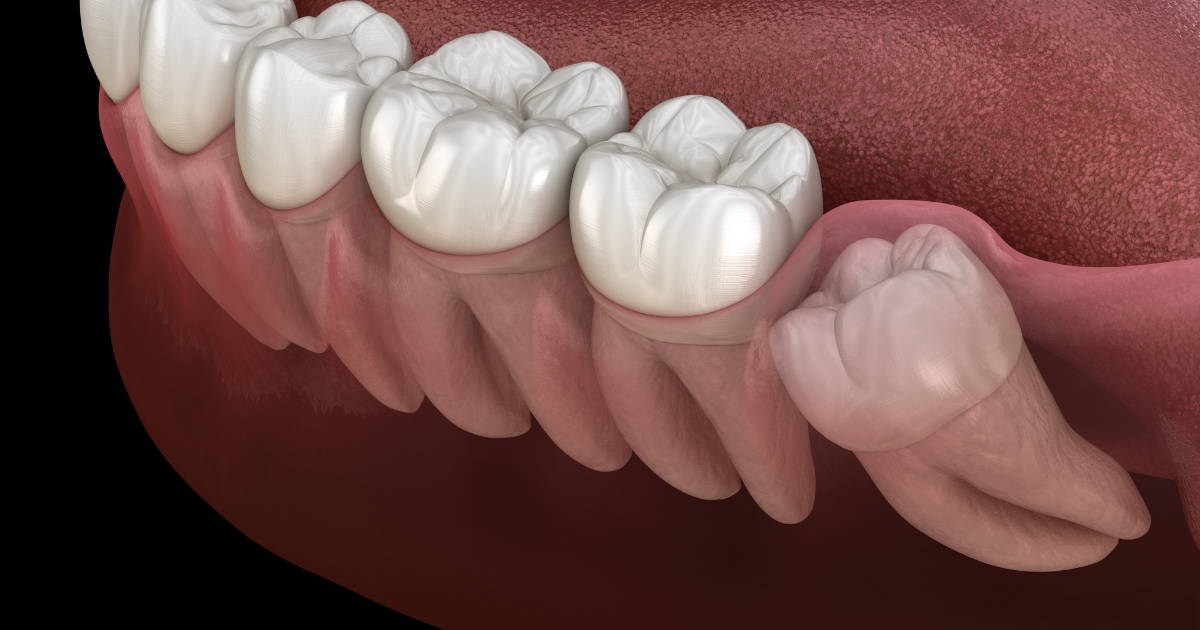

An impacted wisdom tooth is a wisdom tooth that has not erupted from the gum. It's most common in people aged 20 to 25, but it can also be found in children and adolescents as well as adults older than 40. Impacted teeth are more likely to cause problems with your other teeth because they often grow sideways instead of straight up or down as normal ones do.

Impaction is when a tooth can't erupt properly and needs to be removed. Impacted wisdom teeth are not necessary for grinding food, so they have evolved. In some cases, the tooth will need to be dislodged from its attachment to allow it to come out on its own. In other cases, the entire impacted tooth will need removal if there is full impaction or partial impaction of the area where it would normally come through.

Impacted wisdom teeth are horizontal, impacted between the upper front teeth and lower front teeth. Horizontal impactions often cause intense pain when they contact the roots of other healthy teeth or gum tissue.